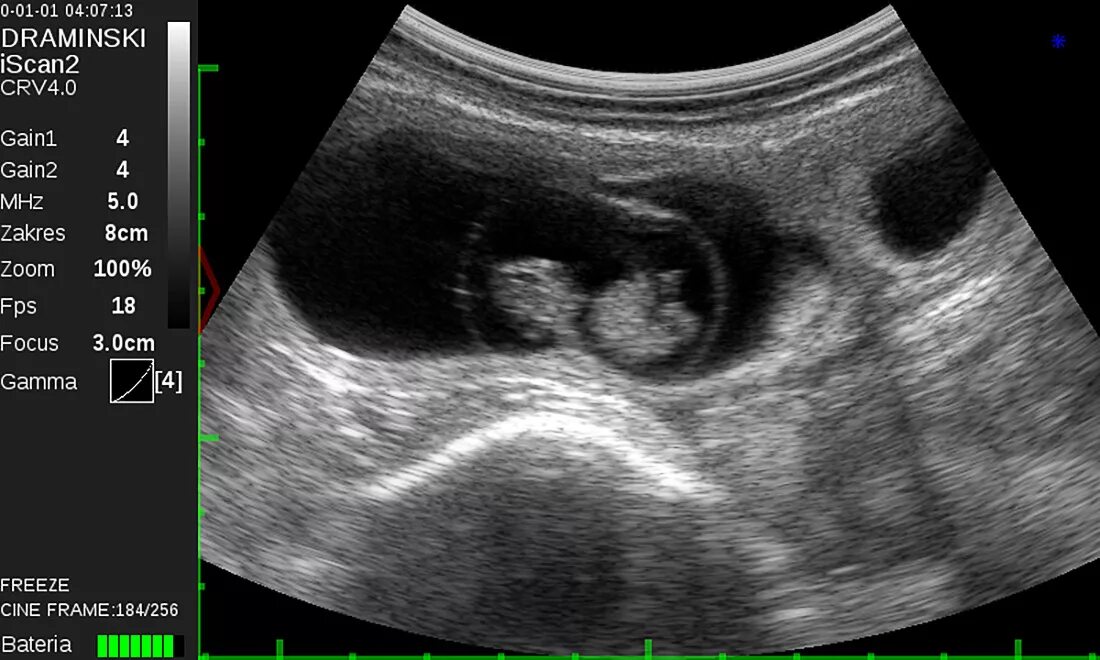

Определение беременности животных